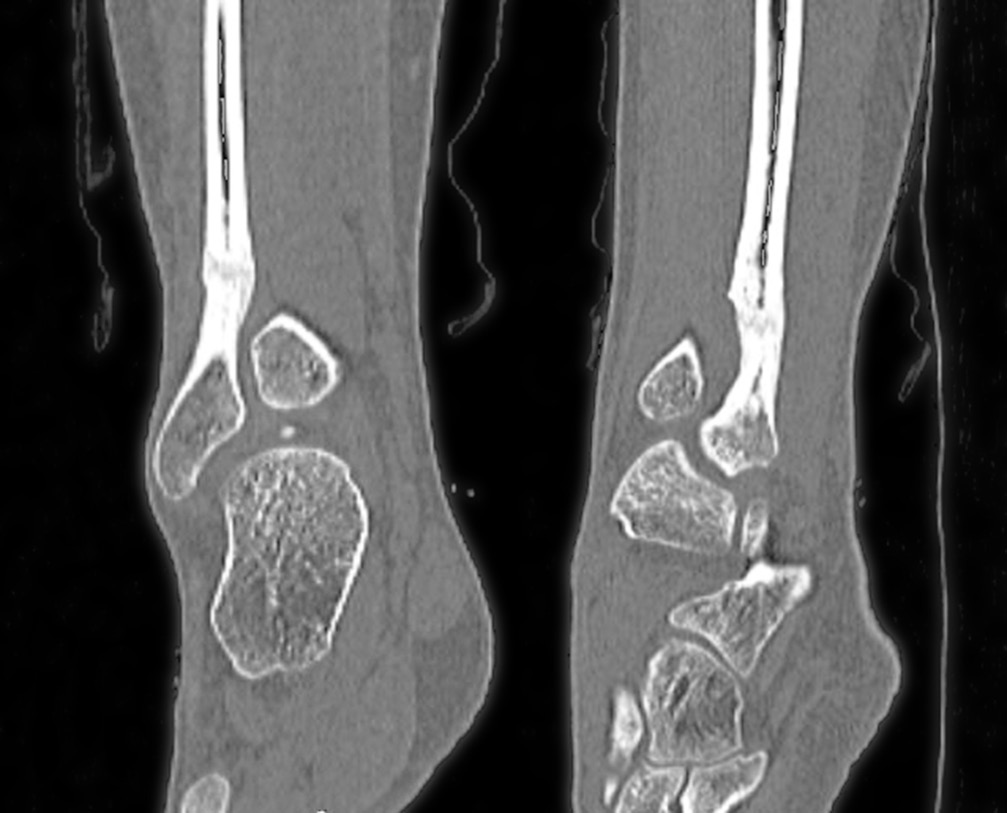

При компьютерной томографии на уровне дистального метадиафиза правой малоберцовой кости определялись деформация, остеосклеротические изменения кости на протяжении 29,0 мм с эндостально расположенными участками высокой плотности; кость локально несколько вздута, отмечались сквозные каналы после туннелизации; узурация и кистовидная перестройка задненаружной поверхности правой таранной кости, утолщение прилежащих отделов суставной капсулы правого голеностопного сустава в задненаружных отделах вследствие незначительного отека, количество синовиальной жидкости было несколько увеличено (рис. 4).

Рис. 4. Мультиспиральная компьютерная томография. Деформация, остеосклеротические изменения кости на протяжении 29,0 мм с эндостально расположенными участками высокой плотности; кость локально несколько вздута

В послеоперационном периоде выраженность болевого синдрома снизилась (до 4–6 баллов по ВАШ). Проводили интенсивные реабилитационные мероприятия. Спустя 4 мес. после резекции склерозированного участка нижней трети малоберцовой кости на контрольной рентгенограмме определялись неоднородность структуры и нечеткость контуров дистального метадиафиза малоберцовой кости с формированием костной мозоли (рис. 6). Признана целесообразной полная нагрузка на конечность. При осмотре через 6 мес. после операции болевой синдром отсутствовал (по ВАШ 0 баллов), наблюдалась потеря чувствительности в области тыльной поверхности стопы. Последующее обследование через 12 мес. после резекции показало отсутствие болевого синдрома и других клинических проявлений. По данным компьютерной томографии прослеживалась отчетливая тенденция к восстановлению органотипической костной структуры нижней трети малоберцовой кости в зоне оперативного вмешательства (рис. 7).

Рис. 6. Рентгенограмма спустя 4 мес. после операции (сегментарной резекции). Образование костной мозоли, заполнение дефекта кости новообразованной костной тканью

Рис. 7. Мультиспиральная компьютерная томография спустя 12 мес. после операции — сегментарной резекции нижней трети малоберцовой кости. Определяются признаки наметившейся дифференциации костной структуры на кортикальный слой и костномозговую полость